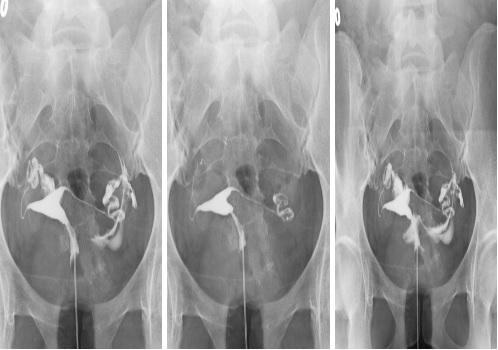

HSG (RAHİM FİLMİ)

HSG Histerosalpingografi işleminin kısaltılmış adıdır. Yani rahim kanalı ve rahim ile yumurtalıklar arasındaki tüpleri gösteren radyolojik bir incelemedir. Bu inceleme röntgen cihazı altında sakinleştirici anestezi ile yapılır. Hasta bu nedenle herhangi bir ağrı hissetmez. Rahim ağzına bir katater yerleştirilir ve bu kataterden kontrast madde verilerek rahim kanalı ve tüpler değerlendirilir. Bu inceleme genellikle çocuk sahibi olamayan anne adaylarında tüplerin açık olup olmadığını göstermek amacıyla yapılır. Ancak rahim kanalı içerisinde olası problemlerde bu inceleme ile saptanır.